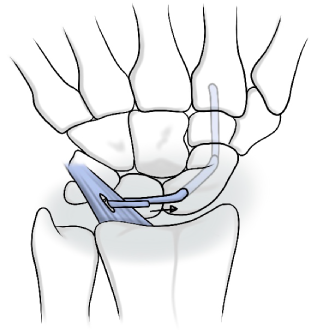

주상월상인대파열

손목 뼈 사이에는 뼈들을 연결하는 내재인대들이 존재하는데, 그 중에서 주상골과 월상골을 연결해주는 인대를 주상월상인대라고 합니다.

주상골과 월상골 사이의 관절면은 서로 협동적으로 움직이는데 여러가지 원인으로 인대 파열되는 질환을 주상월상인대파열이라고 합니다.

• 관절경 또는 절개 하에 봉합

인대재건술 1

인대재건술 2